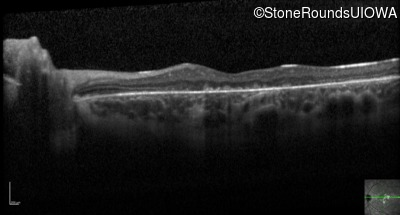

Optical Coherence Tomography - Right - 10/160

Exemplar / OCT Stack

OCT Stack